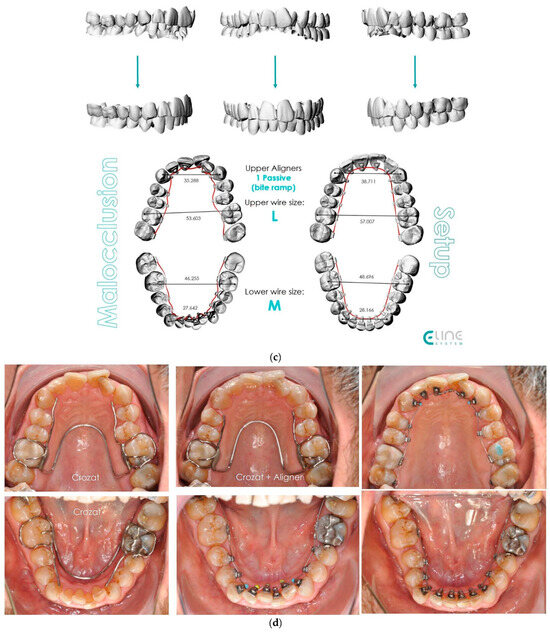

- Case 1: Class II division 2 with deep bite

4.1. Case 1: Class II Division 2 with a Deep Bite